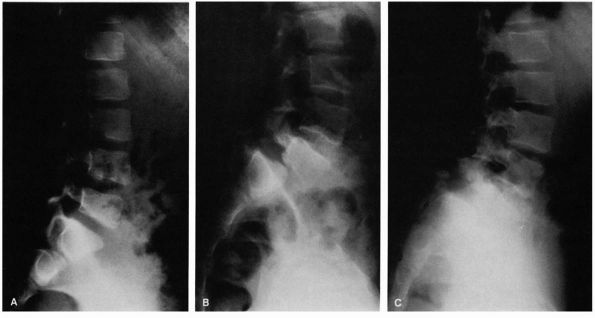

FIGURE 16-25. (A) Six-year-old female gymnast who complained of mild backache. Narrowing of pars interarticularis noted in radiograph. (B)

At age 11, she had increasing pain. Radiograph demonstrates a lytic defect (type IIA) of the pars interarticularis and significant translation; surgery was recommended but refused. (C) Because of increasing pain, surgery was performed at age 12. The preoperative radiograph demonstrates increasing anterior translation and lumbosacral angulation (kyphosis). |